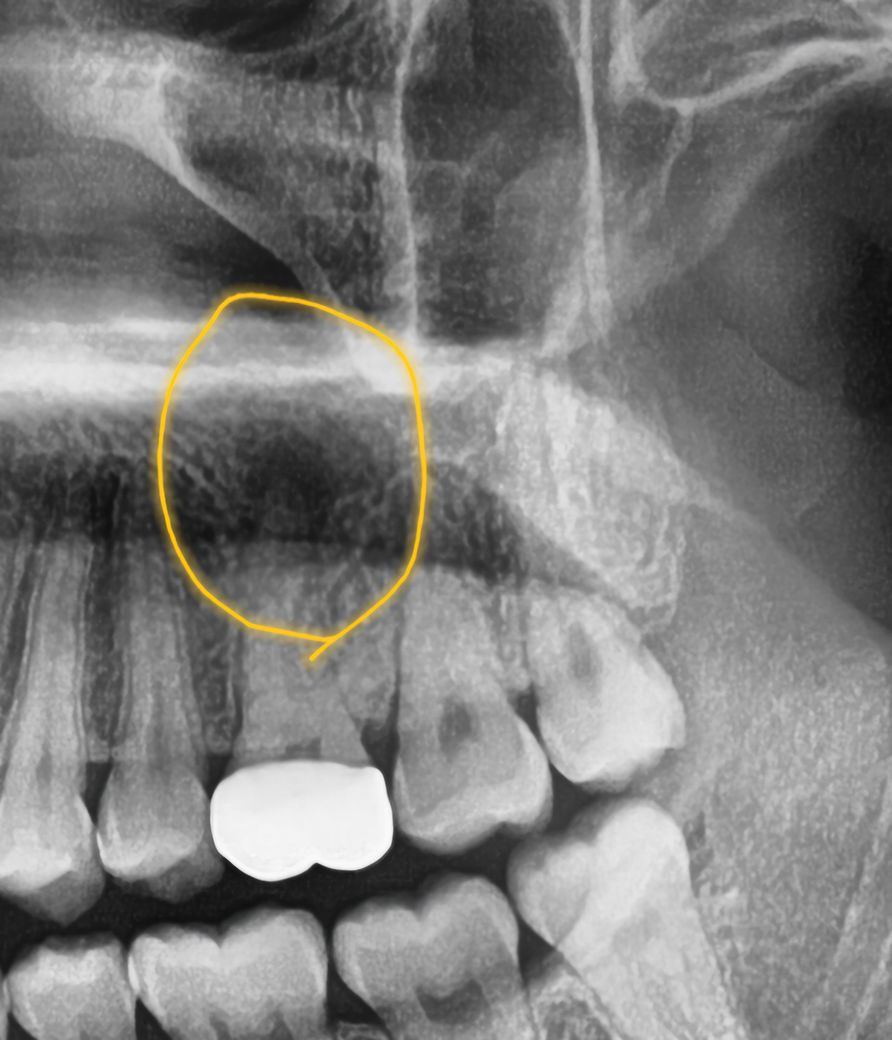

• 3번 째 사진

3개월 전 윗 어금니를 충치 레진치료 후 치아 파절로 지르코니아 크라운을 씌웠는데 그 뒤로 아무 이상이 없다가, 갑자기 4일 전부터 해당 치아가 있는 부위의 볼이 통증은 없고 살짝 부어 올라 치과에 갔더니 [해당 치아의 신경이 죽어있어 통증을 못느꼈던 것이고, 그 안에 염증이 퍼져 위쪽 공기주머니가 있는 곳 까지 번진 것 같다는 진단]을 받았습니다. 이를... 치근단 병소라고 하나요?

저정도 염증이라면 신경치료만 잘하면 크게 문제는 되지 않을것같습니다. 일단 신경치료를 하시는게 좋을것같습니다.

네 치근단 염증이 있는 상태가 엑스레이 상에서도 확인이 됩니다 크라운 뜯거나 구멍을 내고 신경치료 시도하면 됩니다